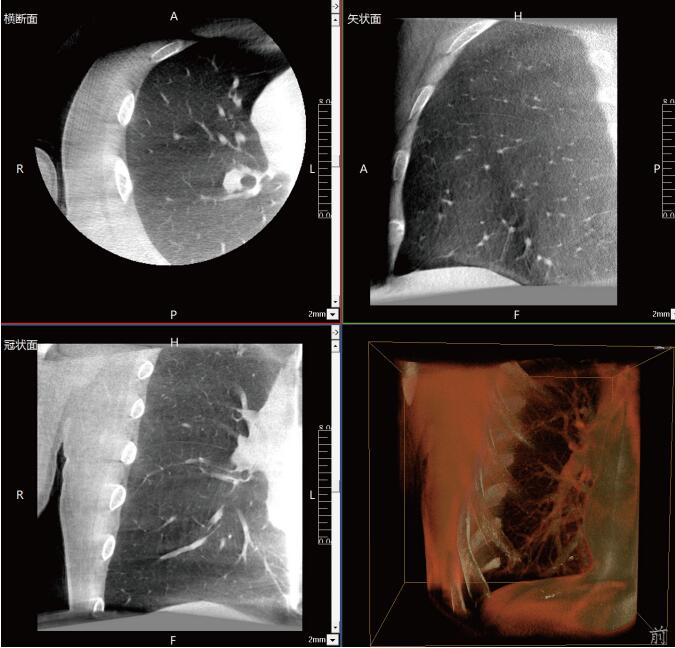

呼吸介入C型臂臨床應(yīng)用-普愛醫(yī)療三維C型臂CT產(chǎn)品說明:

近年來,在肺部手術(shù)領(lǐng)域的應(yīng)用呈現(xiàn)出顯著的增長(zhǎng)態(tài)勢(shì)。這一技術(shù)不僅滿足了臨床指導(dǎo)穿刺、精準(zhǔn)確認(rèn)病變與針尖位置關(guān)系的迫切需求,更通過大量臨床研究的驗(yàn)證,證明了其在肺結(jié)節(jié)診斷、定位及治療中的有效性和安全性。

《中國專家對(duì)CBCT引導(dǎo)下肺結(jié)節(jié)的診斷、定位和治療的共識(shí)》提到C型臂CT系統(tǒng)憑借其強(qiáng)大的功能,能夠充分滿足透視監(jiān)測(cè)、病變與工具位置確認(rèn)、消融區(qū)監(jiān)測(cè)以及并發(fā)癥檢查等多元化的臨床需求。因此,在考慮設(shè)施條件(如導(dǎo)航設(shè)備、手術(shù)室空間)、靶病灶特性(大小、密度)、麻醉方法及干預(yù)路徑(經(jīng)支氣管或經(jīng)胸)等多重因素的基礎(chǔ)上,C型臂CT系統(tǒng)成為了眾多醫(yī)療機(jī)構(gòu)的優(yōu)選方案。

呼吸介入C型臂CT的臨床適應(yīng)癥廣泛,包括支氣管鏡檢查、肺結(jié)節(jié)穿刺活檢、肺結(jié)節(jié)定位、肺結(jié)節(jié)消融以及經(jīng)支氣管肺結(jié)節(jié)診療等多個(gè)領(lǐng)域。其臨床應(yīng)用價(jià)值不言而喻:在經(jīng)支氣管干預(yù)肺結(jié)節(jié)時(shí),透視功能可精準(zhǔn)引導(dǎo)支氣管鏡與活檢鉗直達(dá)靶結(jié)節(jié);重建的三維圖像則能清晰展示干預(yù)工具的位置,確保操作的準(zhǔn)確性。在肺結(jié)節(jié)消融過程中,呼吸介入C型臂CT更是實(shí)現(xiàn)了高精度定位,有效提升了治療效果。